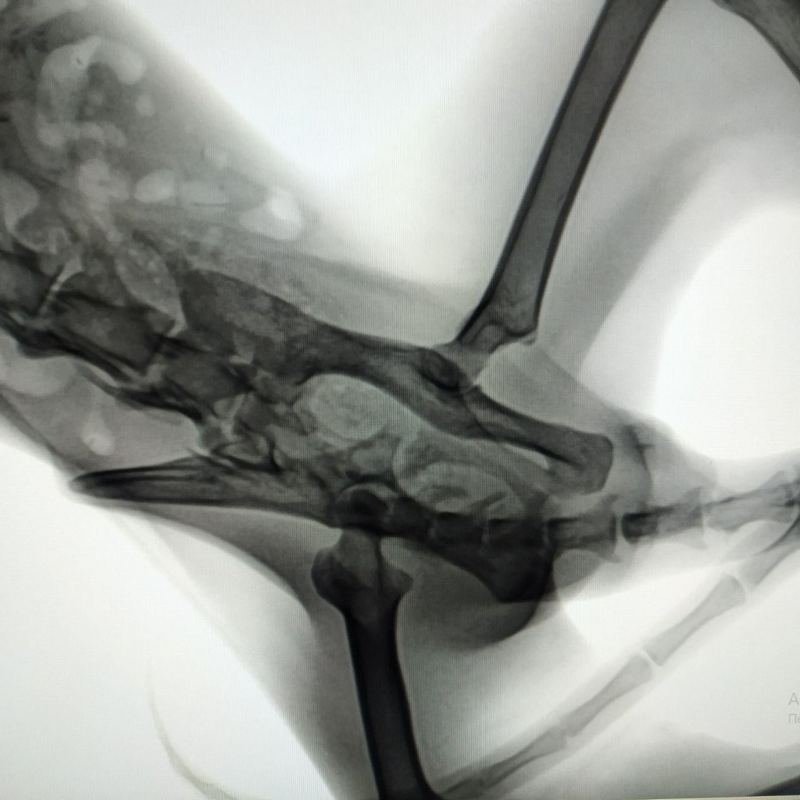

Несмотря на сильную боль, Ежик дополз до мусорных баков, где неравнодушные кормят бездомных котов. Клиника сделала рентген и осмотрела кота, взяла биохимию крови. Его обработали от паразитов. На сегодняшний день долг приюта перед ветлечебницей составляет 1870 гривен, в том числе за корм Royal Canin Gastro и день стационара. Денег нет ни на УЗИ, ни на операцию, ни на лечение.

Кот еле стоит на ногах. Возможно, ему понадобится переливание крови. Сейчас важно срочно начать лечение или хотя бы поддерживающую терапию. Если Ежика прооперируют, то долг увеличится до 1870 гривен. У приюта на попечении еще 25 питомцев, лечение и содержание каждого еженедельно обходится в 1000-3000 гривен. Помните, что ситуацию спасает каждая гривна, поступающая на счет.